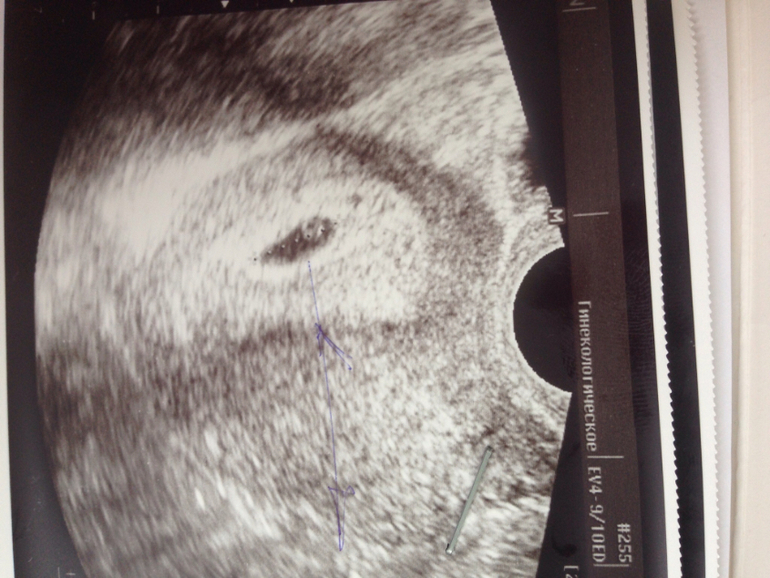

УЗИ, КТГ, доплерНебольшой тонус у нас, удвоили дозу утрожестана. На фото видно что ПЯ капелькой удлиненное, а должно быть кругленькое. Это значит тонус сжимает с двух сторон мою деточку. Я не паникую, у меня ничего не болит, все хорошо, будем подлечиваться слушаться врача и все у нас будет хорошо. Я верю в свою крошку и люблю всем сердцем. Желточный мешочек тоже нашли.